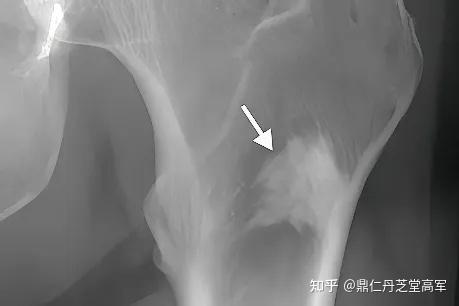

各位大师请判断,骨岛?骨纤?转移瘤?如何进行下一步?